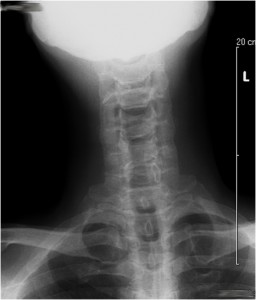

Figure 6. Post-operative anteroposterior (front to back, AP) x-ray